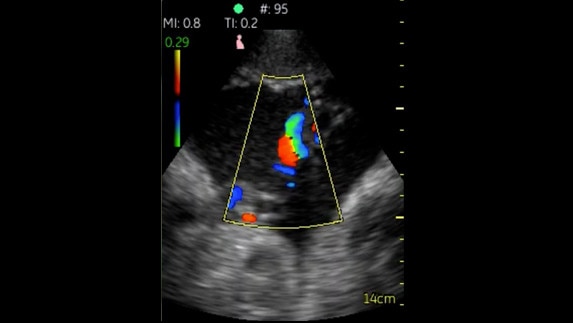

Fazlı Kardiyak